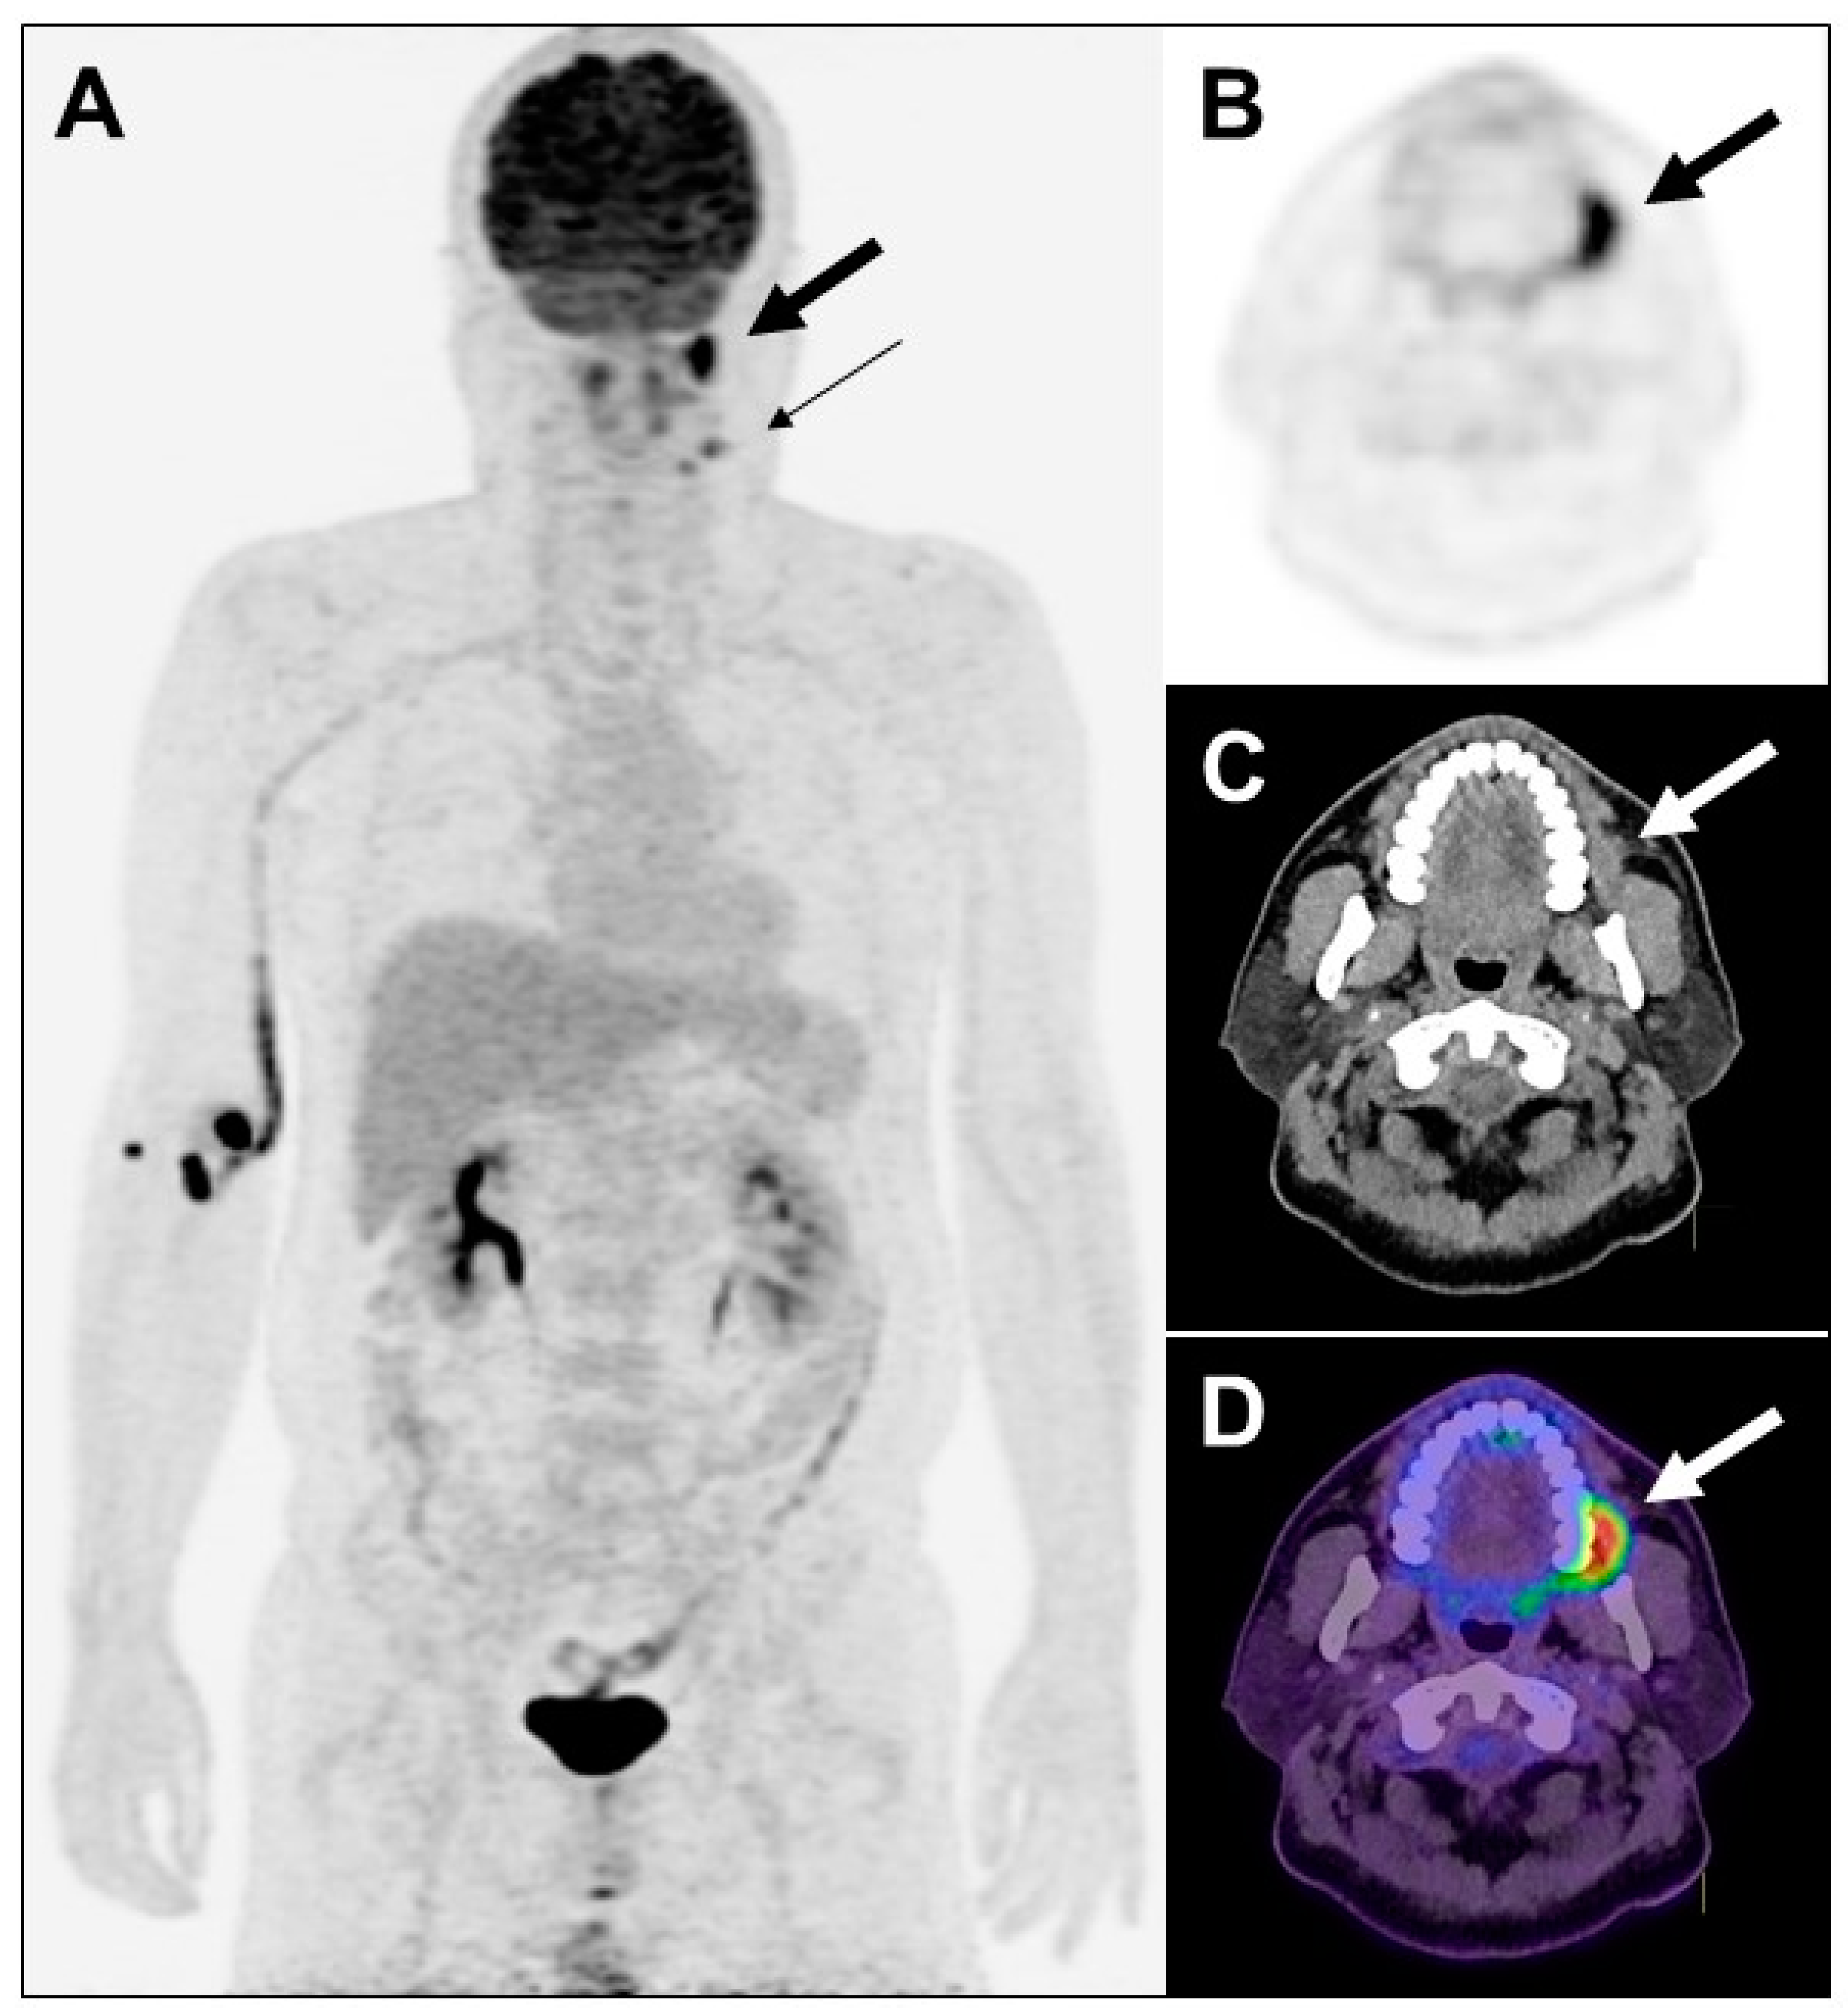

Figure 1. Maximum intensity projection view of PET (A), transaxial views of PET (B), CT (C) and PET/CT fusion (D) images of the illustrative case. A 47-year-old man with history of newly diagnosed left buccal poorly differentiated squamous cell carcinoma, who underwent PET/CT with 18F-fluorodeoxyglucose (FDG), was found to have a focal lesion (2.3 × 1.1 × 2 cm) with moderate increased FDG uptake ((A,B) SUVmax 5.5) in the left buccal ((AD) thick arrow). There were two foci with mild increased FDG uptake (SUVmax 2.3 and 1.3) in the left neck level I ((A) 0.94 cm; thin arrow) and level II (0.8 cm), respectively. Bilateral lungs were clear and no lesion was detected. Image staging was T2N1M0. Four days later, he received wide excision for a left buccal tumor and left modified radial neck dissection. Pathology reported a verrucous and ulcerated tumor measuring 4.1 × 2.7 × 1.3 cm. The modified radical neck dissection samples showed left neck level I one out of five metastatic squamous cell carcinoma, and left neck level II one out of one negative for malignancy. Pathologic staging was pT3N1. Later, he received concurrent chemoradiotherapy with 66Gy/33Fx plus concurrent cisplatin 6 cycles. Patients with a large metabolic tumor volume on FDG-PET may experience poor clinical courses [1].

Diagnostics 13 02706 g001